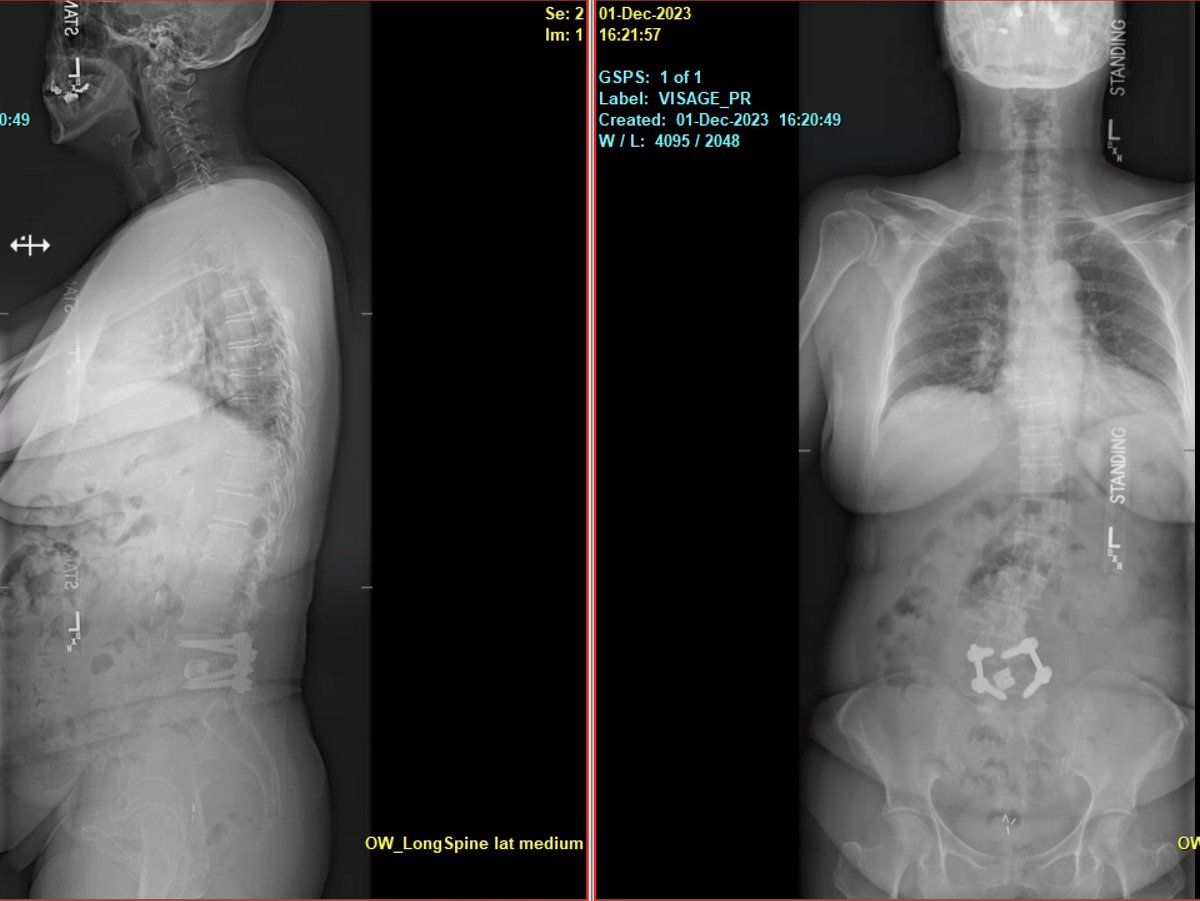

Awake MIS fusion to correct this patient scoliosis. @mayoclinic fellowship @RodNavarroM teaches endoscopic, lateral, MIS awake and deformity. Learn enabling technology & freehand. Accepting fellowship application for 2024-2025. @DoctorQMd @wchrisfox @oakinduroMD @StephenPirrisMD

Pre-and post-op awake MIS fusion to correct this patient scoliosis. @mayoclinic our associate surgeon @RodNavarroMD work hand in hand to learn the latest approach, enabling technology and freehand. Accepting applications for 2024-2025. @DoctorQMd @oakinduroMD @wchrisfox